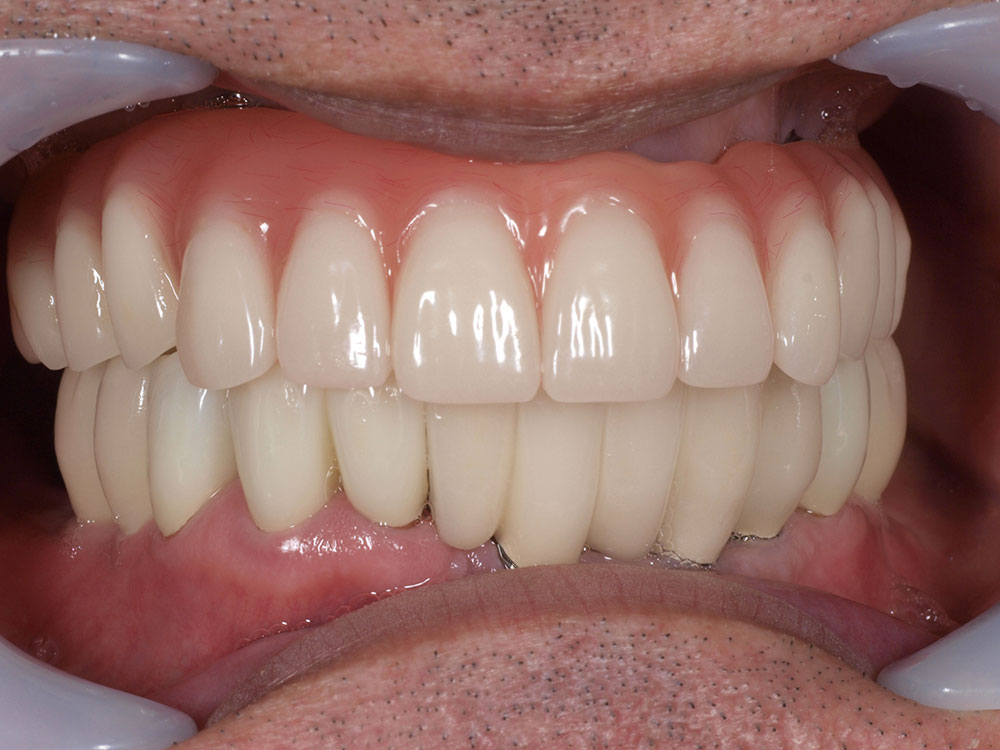

上部構造(人工歯)の装着

インプラントと骨が結合し、口腔内が安定した後、最終的な上部構造を装着します。オールオン4の上部構造は、前歯から奥歯まで連結したブリッジ状の人工歯で、失われた歯茎の部分も人工材料で一体的に作られています。全て一体で作られた人工歯は、歯の大きさ、歯並び、歯茎の引き締まり具合も全て左右対称に理想的な状態にデザインされており、優れた審美性を提供します。唇の張りまで回復するため、清潔で若々しい印象を目指すことができます。

症例紹介

- 主訴

- 入れ歯が合わない。食べにくい。人生を豊かにしたい。

- 処置内容

- 上顎4本で12歯(オールオン4)、下顎4本5歯。

上下抜歯即時埋入、即時荷重(手術当日にインプラントの上に仮歯装着)

- 治療費用

- 上顎:約290万(税込)、下顎:約210万円(税込)

- 治療期間・通院回数

- 上顎:9か月/9回

下顎:6か月/7回

- リスク

- 術後の腫れ、痛み(ピークは3日後、1週間で軽減)

上部構造物、仮歯の破折、人工歯根脱落リスクがあります